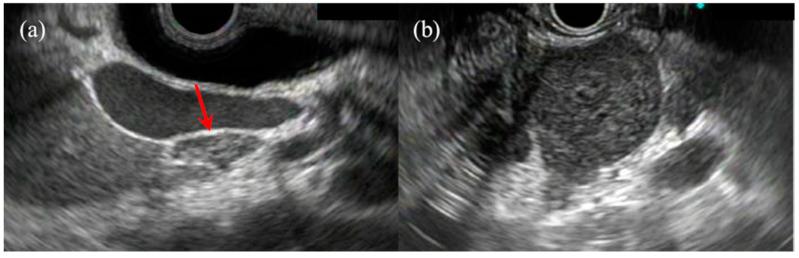

使用内镜超声诊断胰腺实性病变、上皮下病变及淋巴结

Diagnosis of Pancreatic Solid Lesions, Subepithelial Lesions, and Lymph Nodes Using Endoscopic Ultrasound.

Currently, endoscopic ultrasound (EUS) has become widely accepted and has considerable advantages over computed tomography (CT) and other imaging modalities, given that it enables echostructure assessment in lesions with <1 cm diameter and permits high resolution imaging. EUS-guided tissue acquisition (EUS-TA) provides consistent results under ultrasound guidance and has been considered more effective compared to CT- or ultrasound-guided lesion biopsy. Moreover, complication rates, including pancreatitis and bleeding, have been extremely low, with <1% morbidity and mortality rates, thereby suggesting the exceptional overall safety of EUS-TA. The aggressive use of EUS for various lesions has been key in facilitating early diagnosis and therapy. This review summarizes the diagnostic ability of EUS for pancreatic solid lesions, subepithelial lesions, and lymph nodes where it is mainly used. EUS has played an important role in diagnosing these lesions and planning treatment strategies. Future developments in EUS imaging technology, such as producing images close to histopathological findings, are expected to further improve its diagnostic ability. Moreover, tissue acquisition via EUS is expected to be used for precision medicine, which facilitates the selection of an appropriate therapeutic agent by increasing the amount of tissue collected and improving genetic analysis.

目前,鉴于内镜超声(EUS)能够对直径小于1 cm的病变进行回声结构评估并实现高分辨率成像,它已被广泛接受,相对于计算机断层扫描(CT)及其他成像方式具有显著优势。EUS引导下的组织获取(EUS-TA)在超声引导下可提供一致的结果,并且与CT或超声引导下的病变活检相比,被认为更有效。此外,包括胰腺炎和出血在内的并发症发生率极低,发病率和死亡率均低于1%,这表明EUS-TA具有极高的总体安全性。积极将EUS用于各种病变是促进早期诊断和治疗的关键。本综述总结了EUS对胰腺实性病变、上皮下病变以及主要应用EUS的淋巴结的诊断能力。EUS在诊断这些病变及制定治疗策略方面发挥了重要作用。预计EUS成像技术的未来发展,如生成接近组织病理学结果的图像,将进一步提高其诊断能力。此外,通过EUS进行组织获取有望用于精准医学,通过增加采集的组织量和改进基因分析来促进合适治疗药物的选择。